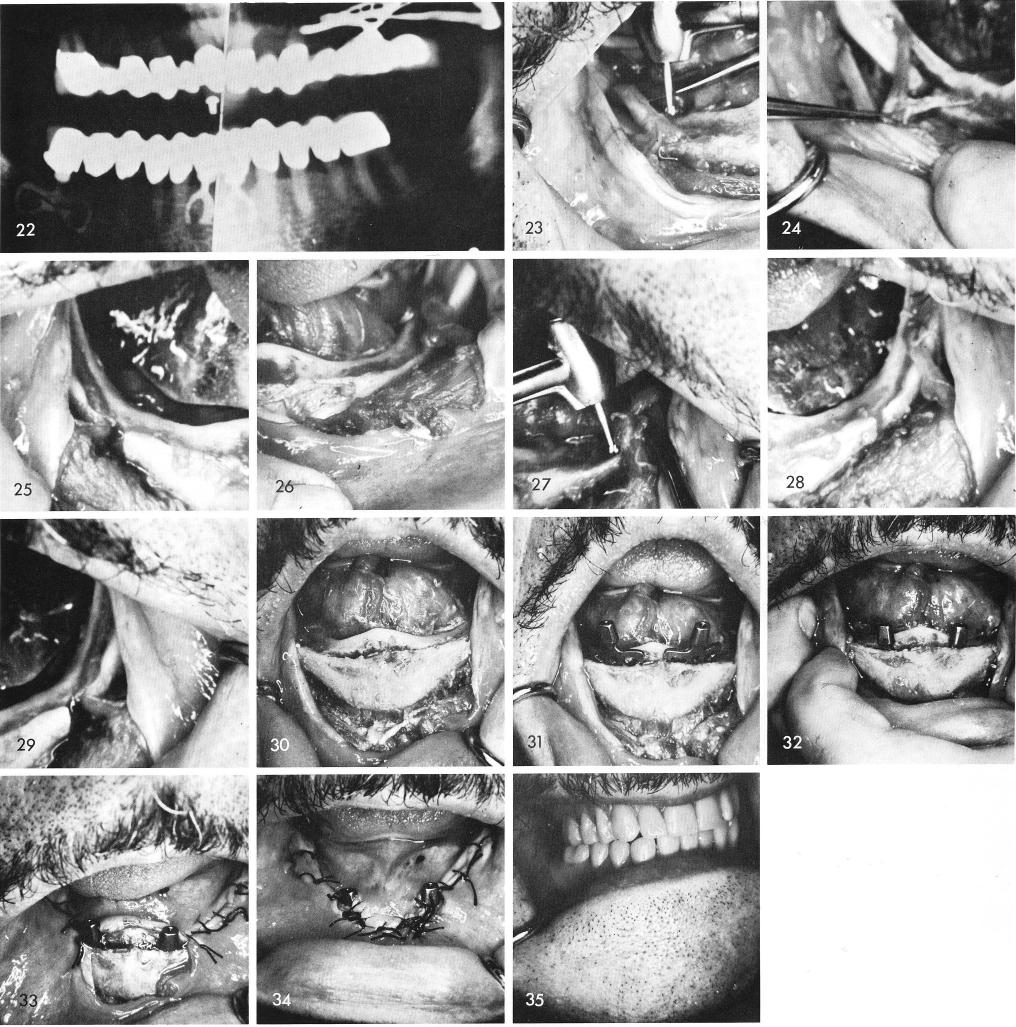

At times, due to extreme resorption of the posterior edentulous areas of bone the inferior alveolar nerves and the mental bundles are totally exposed, fig. 23. With a round bur, the author has often created his own inferior alveolar canal and mental foramen, fig. 24, into which the inferior alveolar nerve and mental branch were placed into, fig. 25.

The same is repeated on the other side of the arch, figs. 26, 27, 28, 29. Anteriorly where there still remains sufficient bone a groove is made, fig. 30, to allow the bladevents, fig. 31, to be tapped properly into the bone, fig. 32. The tissues are then sutured closed, figs. 33, 34, and a snap-on removable denture is fabricated, supported by the anterior blades, fig. 35.

1 Exposed inferior alveolar nerves & mental bundles in resorbed mandible